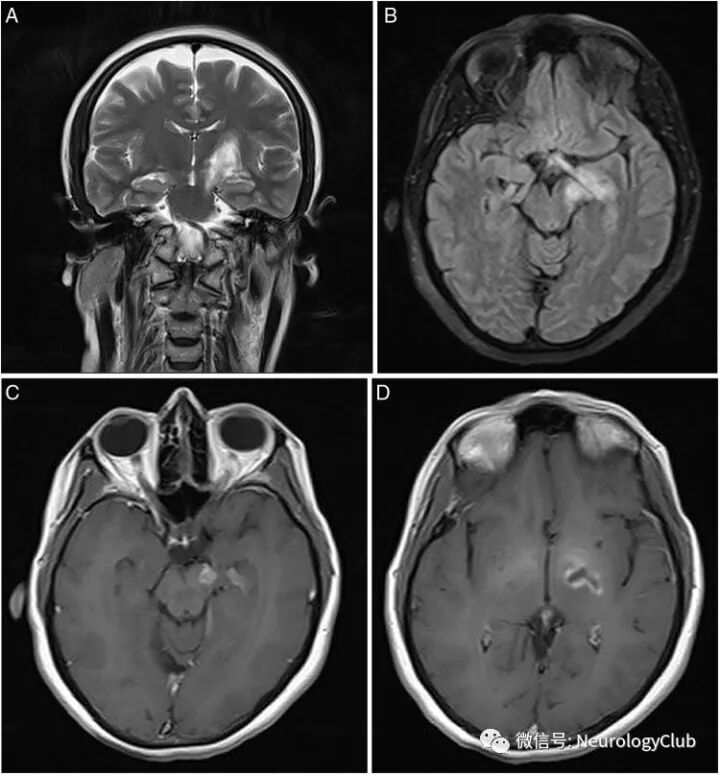

非实质神经白塞病以脑静脉系统受累为主,可表现为静脉窦(最常见闭塞部位为上矢状窦和横窦)或静脉血栓形成,也可伴有动脉瘤等。

脑膜病变

(图21:NBD患者T1增强可见软脑膜强化)

(图22:A-B:增强T1可见弥漫硬脑膜强化;C-D:激素治疗后2月T1增强病灶较前改善)

脑动静脉系统受累

(图23:A-B:貌似急性脑梗死的右侧脑桥病灶;C:MRA可见基底动脉中段闭塞;D-E:MRV可见左侧乙状窦和颈内静脉远端以及直窦血栓形成

(图24:a:T1WI;b:MRV;可见右侧横窦血栓形成)

(图25:A:可见上矢状窦后半部充盈缺损;B:右侧额叶和左侧顶叶高信号病灶)